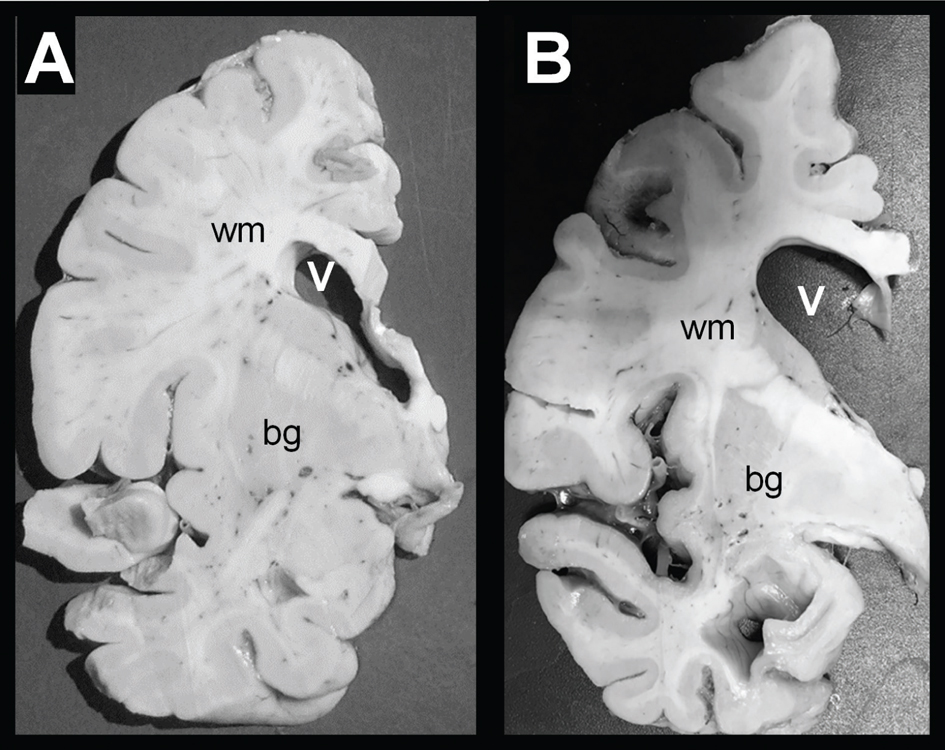

White matter degeneration is a major and consistent but vastly under-studied abnormality in AD (Figure 1). Its occurrence was initially characterized in 1986 by Brun and Englund (4, 5) and subsequently shown to be an early pre-clinical abnormality (6). WM atrophy in AD is most pronounced in the parietal and temporal lobes, followed by the frontal lobes, whereas the occipital lobes tend to be spared (6). Consequently, the severities of WM atrophy correspond with the distribution and degree of cerebral cortical pathology. WM degeneration in AD is associated with loss of myelin and myelinated axons, together with dysfunction or loss of oligodendrocytes, increased activation of astrocytes, that is gliosis, and microvascular disease (79). Leukoaraiosis, an extreme form of WM degeneration in which the loss of myelinated axons is extensive and associated with WM hyperintensities by magnetic resonance imaging (MRI) (79), is most prominently distributed in periventricular and central compared with subcortical WM (5, 6, 1015).

Figure 1 White matter atrophy in AD. Postmortem coronal slices of the left cerebral hemisphere from patients with (A) normal aging or (B) advanced AD. Panels A and B show approximately the same coronal slice levels depicting the cingulate gyrus, corpus callosum, basal ganglia (bg), central and periventricular posterior frontal white matter (wm) and lateral ventricle. Note the markedly atrophic white matter and associated ex vacuo enlargement of ventricles (V) in (B) AD relative to (A) control.